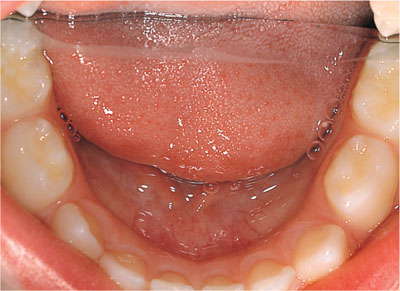

maintain space for the permanent teeth (Fig 1-5)

Fig 1-5 Primary teeth act as a natural space maintainer for the permanent teeth.